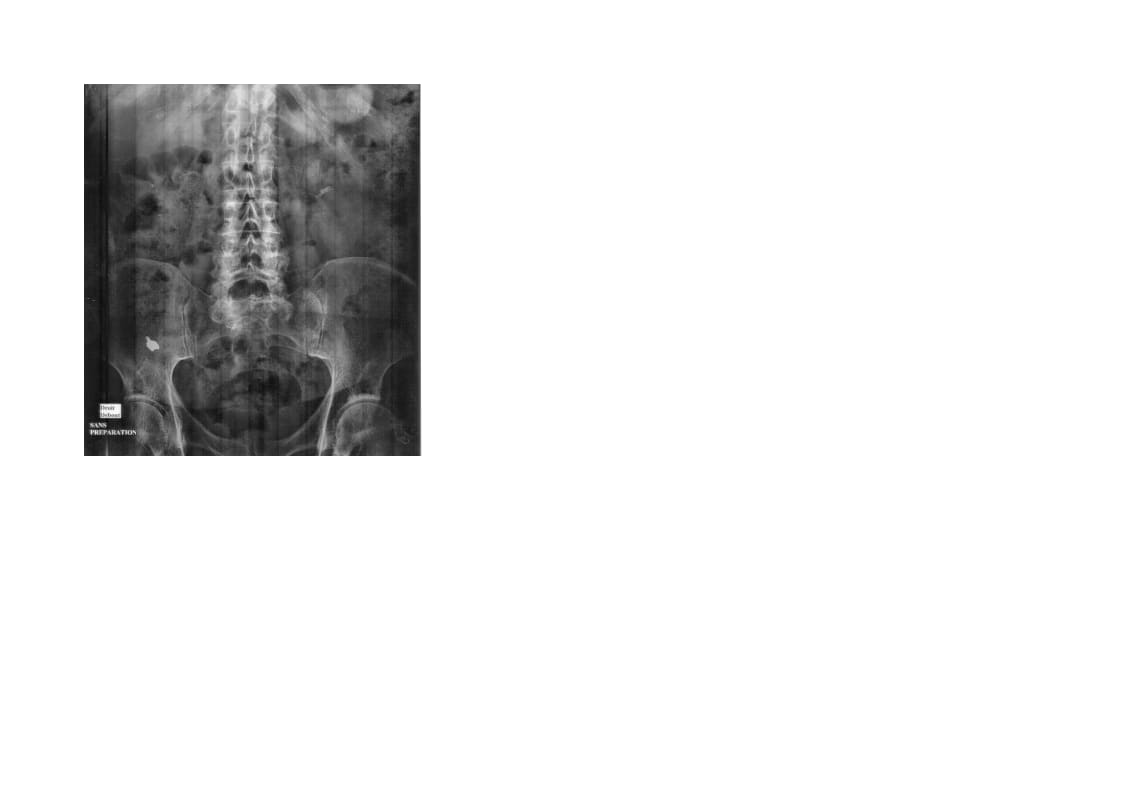

Faire pratiquer une ASP?

Une petite radio abdominale de contrôle pour être sur et pour se rassurer

Commee zorba, une radio thoraco abdominale de controle normalement 5 jours apres quand absence" de signes, , donc ici 15 jours, oui. Dans mes 4 ou 5 cas en 35 ans, jamais eu besoin d'intervention, c'etait expulsé avant les 5 jours!

Comme les copains, radio abdo et thoracique, tu peux inhaler sans signes cliniques...

Où est Charlie ?